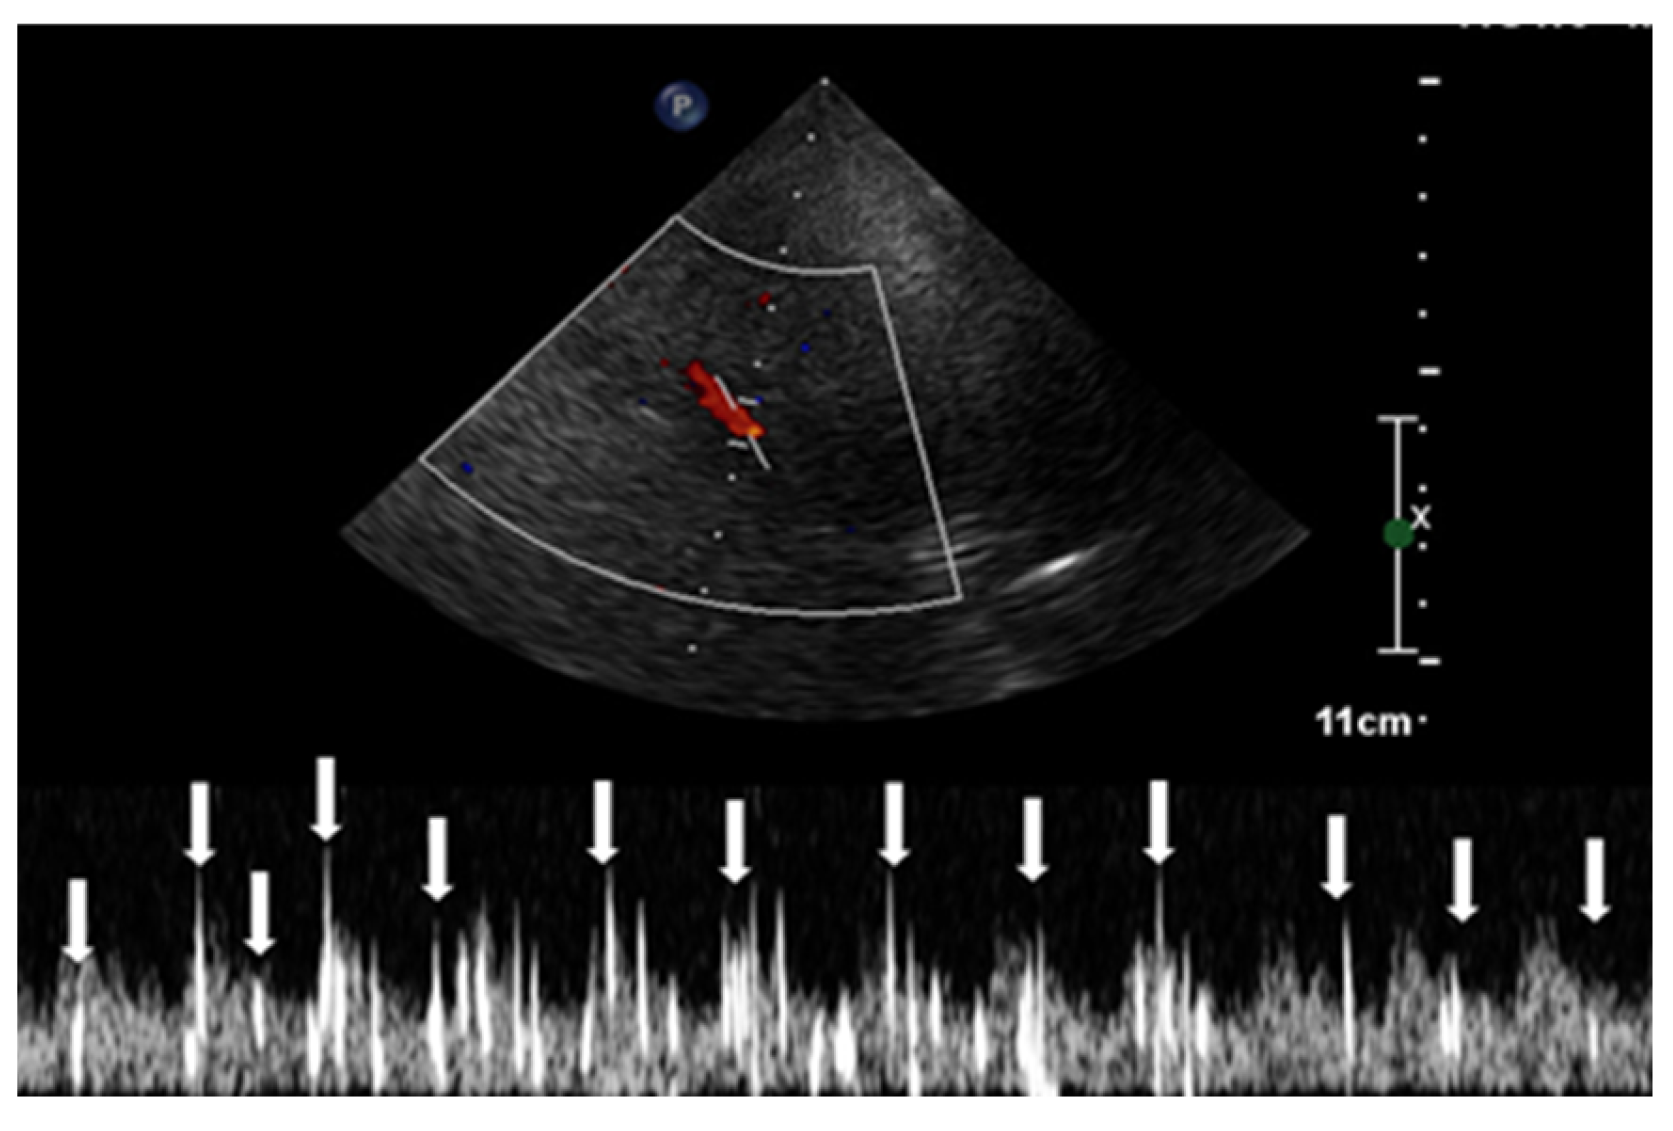

High Intensity Transient Signals (HITS) via Transcranial Doppler Transcranial Doppler With Bubble during bubble study, the spectral doppler easily detects air bubbles that pass through the cerebral arterial circulation (such as the mca). we read with interest the recent article by romero et al highlighting ischemic cerebrovascular complications. most experts think that a better way to assess whether a pfo is likely to produce a stroke is to do. Transcranial Doppler With Bubble.

Transcranial Doppler With Bubble transcranial doppler is utilized to investigate the intracranial vasculature for various purposes. an intracranial neurovascular exam is also known as a transcranial doppler (tcd) study. transcranial doppler is utilized to investigate the intracranial vasculature for various purposes. we read with interest the recent article by romero et al highlighting ischemic cerebrovascular complications. transcranial doppler (tcd) bubble test can detect or rule out pfo with a sensitivity of 97% and specificity of 93% compared with tee (18,. most experts think that a better way to assess whether a pfo is likely to produce a stroke is to do a transcranial doppler study (tcd) with a bubble. during bubble study, the spectral doppler easily detects air bubbles that pass through the cerebral arterial circulation (such as the mca).

we read with interest the recent article by romero et al highlighting ischemic cerebrovascular complications. during bubble study, the spectral doppler easily detects air bubbles that pass through the cerebral arterial circulation (such as the mca). transcranial doppler is utilized to investigate the intracranial vasculature for various purposes. an intracranial neurovascular exam is also known as a transcranial doppler (tcd) study. transcranial doppler (tcd) bubble test can detect or rule out pfo with a sensitivity of 97% and specificity of 93% compared with tee (18,. most experts think that a better way to assess whether a pfo is likely to produce a stroke is to do a transcranial doppler study (tcd) with a bubble.